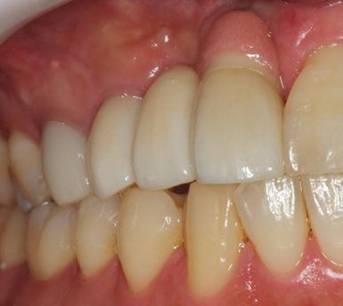

術後。上部構造はハイブリッドレジンです。しっかり嚙めるようになり喜んでいただきました。

上部構造装着後6年。ハイブリッドレジンを使用したため、少し艶がなくなってきました。上部構造の材料には金属、ハイブリッドレジン、セラミックなどがあります。セラミックはきれいですが欠けやすいため、最近はフルジルコニアを使っています。

上顎 少しすり減ってきました。

下顎。12か月に一度メインテナンスをしています。

インプラント装着後6年。順調に経過しています。12か月毎のメインテナンスをしています。